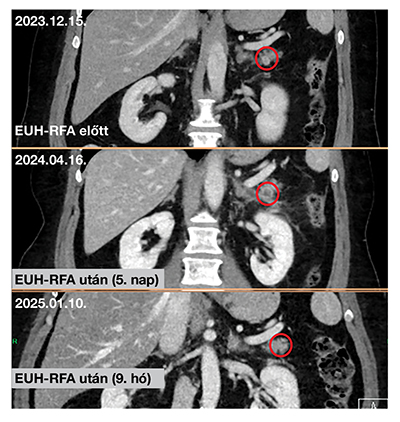

Az RFA-t mind az 5 esetben sikeresen elvégeztük. A beavatkozással közvetlen összefüggésben álló korai szövődményt egy alkalommal sem észleltünk. Egy betegünk a beavatkozást követő ötödik napon hasi fájdalom miatt hospitalizációra szorult; a sürgősséggel elvégzett vizsgálatok perforációt vagy hasnyálmirigy-gyulladást nem igazoltak (amiláz-lipáz normál; CRP: 13,6 mg/dl). Az esetet szúrcsatorna-irritációnak véleményeztük, amely rövid antibiotikumkúra és fájdalomcsillapítás mellett hamar oldódott. Az ablációs kezelés hatására már jól látható volt a tumorban a centrális elhalás a panasz miatt végzett korai CT-felvételeken is. A többi betegünk esetében sem korai, sem késői szövődményt nem regisztráltunk. Az onkológiai utánkövetést klinikai állapotfelmérés mellett kontrasztanyagos, hasi CT-vizsgálatokkal (3, 6 és 12 hónap) és ismételt laborvizsgálatokkal végeztük. Három betegnél az egyéves kontroll képalkotó vizsgálat során az elváltozás teljes vagy részleges (>50%) regressziót mutatott (4. ábra). Egy páciensnél a regresszió mértéke 40%-nak mutatkozott, és a chromogranin A értéke is emelkedett, így itt ismételt RFA-t végeztünk a korábbival megegyező beállításokkal; a további utánkövetéses adatok még nem állnak rendelkezésre. Az utolsó beteg esetében a harmadik hónapnál ismételt CT-vizsgálat során az elváltozás még változatlan méretűnek mutatkozott. Az EUH-RFA-kezelésen átesett betegeink utánkövetését és az új betegek bevonását jelenleg is folytatjuk.